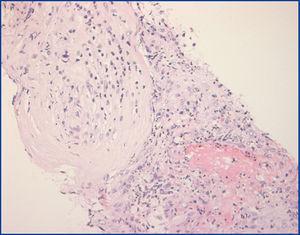

Ante los datos de vasculitis activa, se inicia tratamiento con tres bolos intravenosos de 1 g de 6-metil-prednisolona seguidos de prednisona oral 1 mg/kg/día y ciclofosfamida oral 2 mg/kg/día iniciando hemodiálisis. A los 15 días se realiza una segunda biopsia renal que muestra nuevas lesiones vasculíticas (figura 2). Se asocia plasmaféresis, realizándose cuatro sesiones por alteraciones en la coagulación. La ciclofosfamida se suspende por trombopenia y leucopenia. Tras el fallo de los procedimientos terapéuticos anteriores, se decide tratamiento con rituximab una dosis semanal intravenosa de 375 mg/m2 durante cuatro semanas y pauta descendente de esteroides. En los tres meses siguientes presenta mejoría de función renal, negativización de p-ANCA y descenso de eosinófilos, retirándose la diálisis. Por la afectación pulmonar se mantiene prednisona 5 mg/día, y no se administran más dosis de rituximab (figura 3). A los cinco años podemos hablar de remisión de la enfermedad. No ha presentado complicaciones infecciosas.

Figura 2. Segunda biopsia renal (H-E).